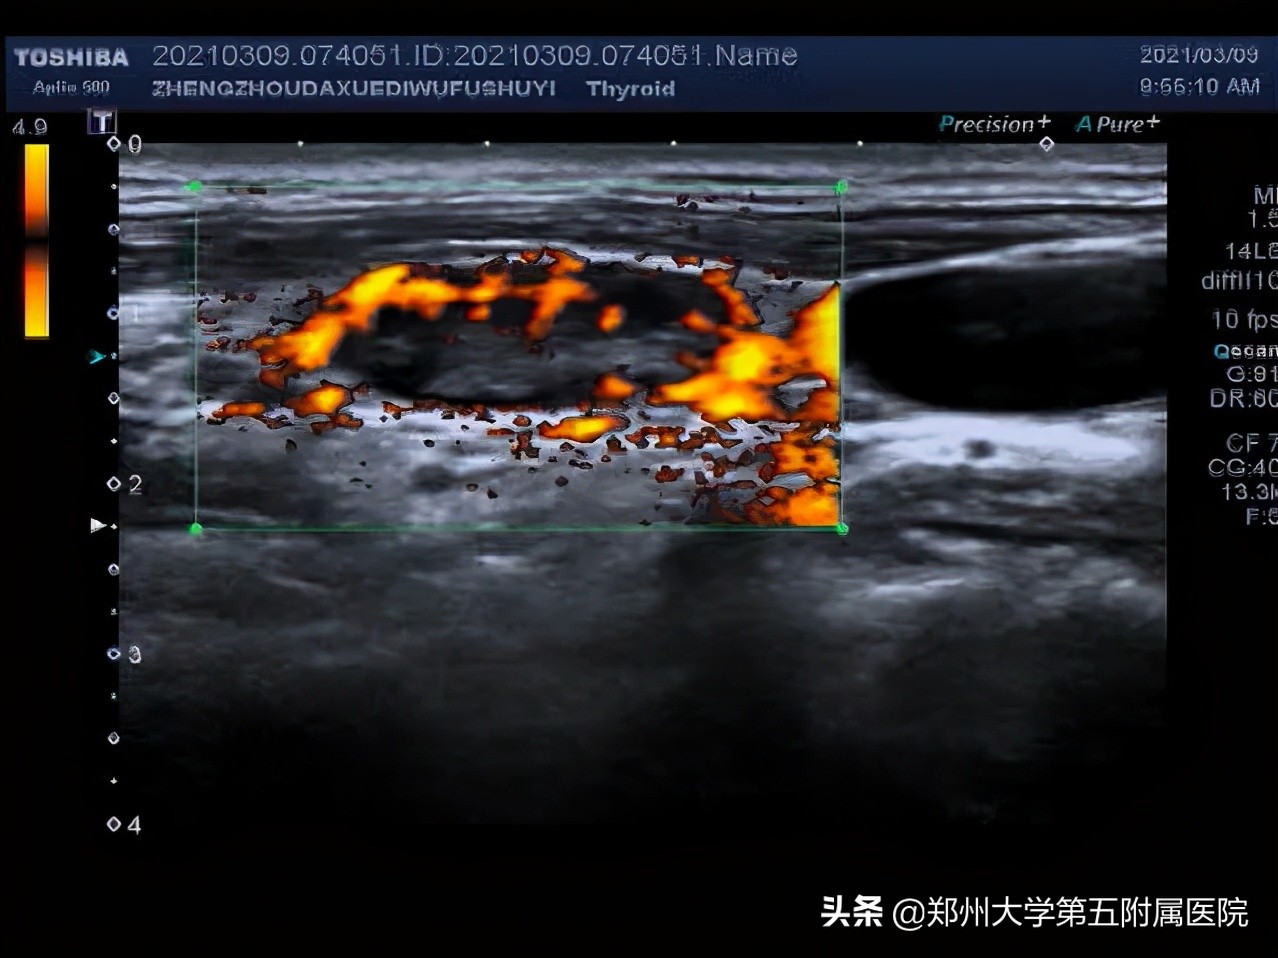

3.淋巴结血流为周边型,没有淋巴门。

2.不疼不痒、进行性肿大淋巴结:这些淋巴结要注意了!需要到医院做彩超检查,检查前不需要特殊准备。超声看到淋巴结内有液化、钙化、淋巴结变圆,皮髓质分界不清,淋巴结相互融合、淋巴结血流为周边型、淋巴门消失等就可能是淋巴瘤、结核、转移性肿瘤、结节病等,需告知临床医生进行进一步检查明确诊断。